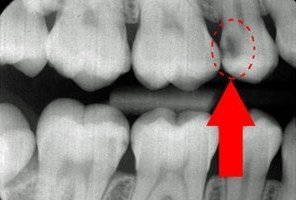

Caria dentară este reprezentată pe radiografie de o zonă gri spre negru prezentă pe suprafața dintelui. De asemenea, cariile pot ataca și dinți cu lucrări protetice chiar la joncțiunea dintre substanța naturală ș proteză.

Resorbțiile osoase sunt reprezentate de coborârea sau urcarea liniei de os sub linia normală (limita dintre coroana dentară naturală și rădăcină), lăsând zone de rădăcină descoperite și înconjurate de suprafețe negre.